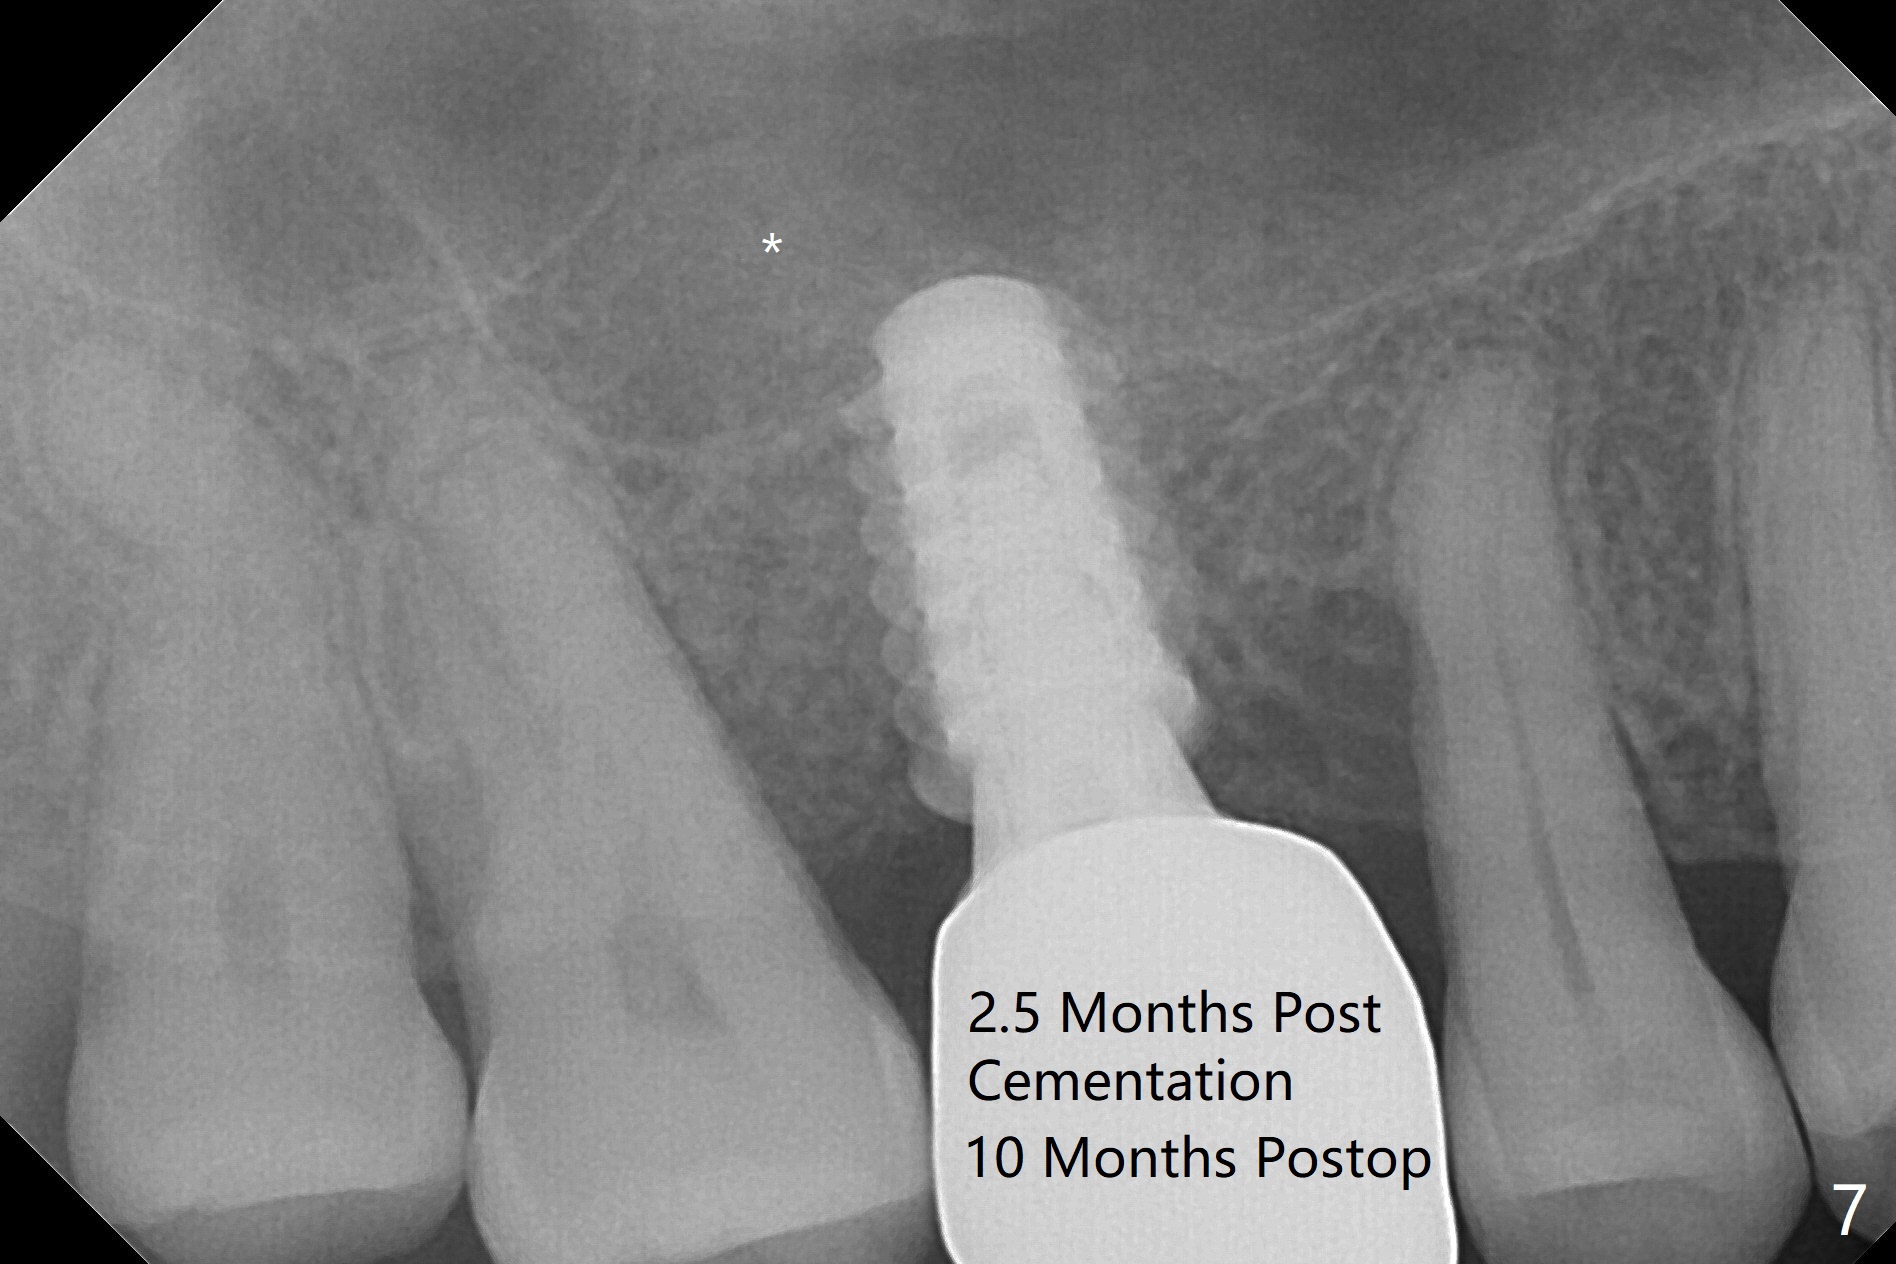

After extraction and debridement, osteotomy is initiated in the mesiobuccal socket free hand. Since the remaining bone is ~ 2 mm, the sinus floor is perforated suddenly. Fortunately the sinus membrane is not, as related to its thickening (similar to water ballooning, without symptom). Use 2-3.5 mm drills to enlarge the bony perforation (mainly lateral movement), followed by pushing bone graft upstairs with a curette (Fig.1 *); insert a 4x9 mm dummy implant (Fig.1) to determine the length of the final implant (Fig.2,3). A drawback of this case is the low torque (<20 Ncm), considering the thin bone. Following deeper implant placement, a 5.2x6(2) mm temporary abutment is placed for an immediate provisional to keep large amount of bone graft in place (Fig.3 *). There is no pain 1 week postop, while the immediate provisional remains stable partially because of the temporary abutment (Fig.4 ^). Four months postop, the temporary crown is loose. After removal of the temp and the temp abutment, gingival cuff is erythematous. A 6x4 mm healing abutment is placed. The bone graft (Fig.3 *) appears to have attached to the root of the neighboring tooth and the implant threads 7 months post op (COVID 19, Fig.5 arrowheads)). The bone graft appears to continue to merge with the neighboring root, bone and implant 10 months postop (2.5 months post cementation, Fig.6). The bone graft in the sinus seems to collapse and condense 10 months postop (Fig.7 *).